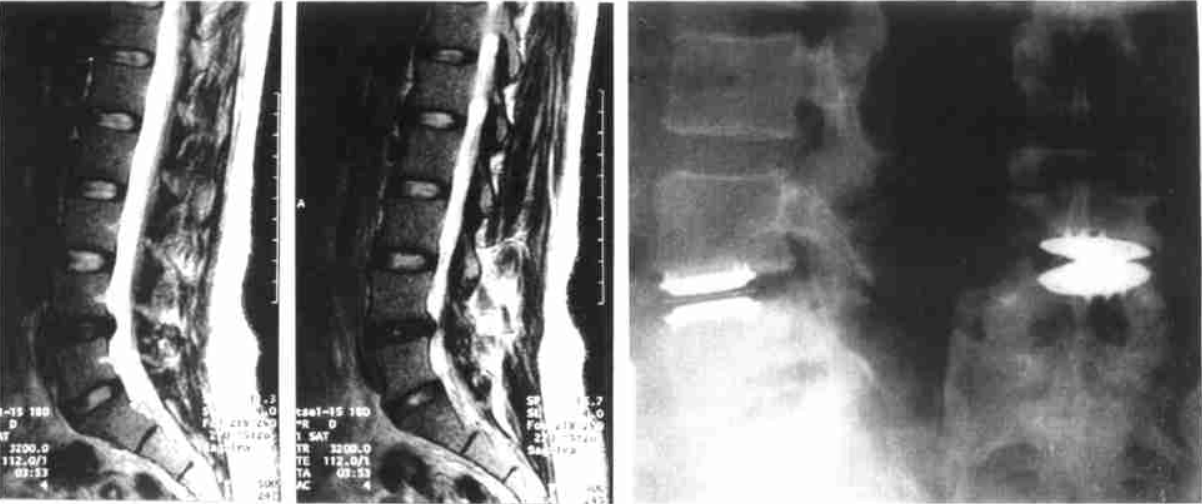

②腰椎CT(腰椎椎体CT或腰椎间盘CT)

图片 14336

③腰椎磁共振(腰椎MRI)。

图片 14338